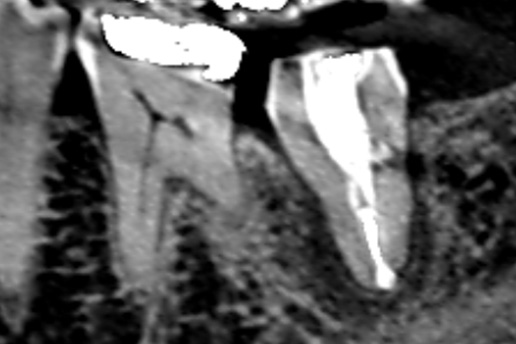

■破折歯

他院で歯が割れているため抜歯と言われたケース。当院で診断したところ破折ではないことが判明し、適切な処置で抜歯せず歯を再生させた。